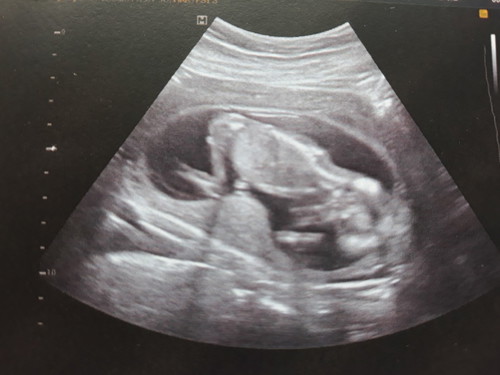

มีบ้านไหนนอนท่านี้ไหมคะ หนีบไว้ไม่โชว์แม่เลย

15 week ไม่เห็นเลยลูกหนีบไว้ พอเหยียดขาละโชว์ตูดอีก เห็นตรงตูดขาวๆ ไม่รู้ว่า ชายหรือหญิง หรือเป็นเท้าอีกข้าง แม่ต้องไปลุ้นครั้งหน้าอีก

15 w ค่ะโชว์ตั้งแต่ครั้งแรกที่ดูเพศ สงสัยอยากให้ซื้อของรอแล้วแต่จิงๆก็แอบตรวจนิฟตี้ไปแล้ว 555

บ้านนี้ตอน 13w ก็หันหนีเหมือนกันค่ะ โชคดีที่ตรวจนิฟตี้ เลยรู้ว่าสาวน้อย 😂